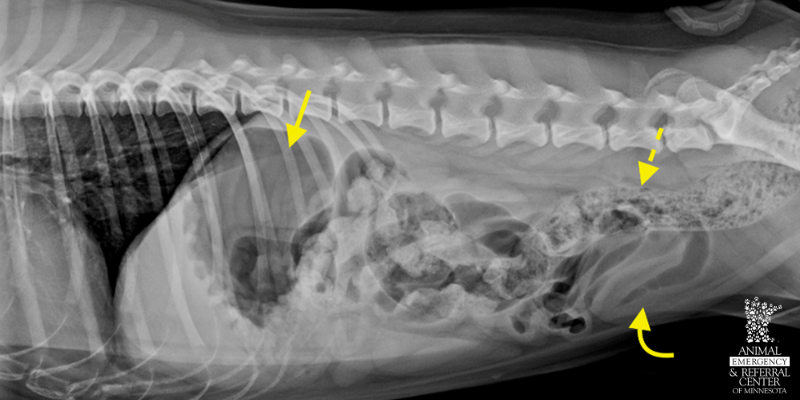

Abdomen x-ray in a young vomiting dog. The stomach is mild to moderately filled with gas (arrow), small intestines mildly filled with gas and fluid (curved arrow), and feces in the colon are less formed than normal (dotted arrow). These findings are suggestive of non-specific inflammation of the intestinal tract.